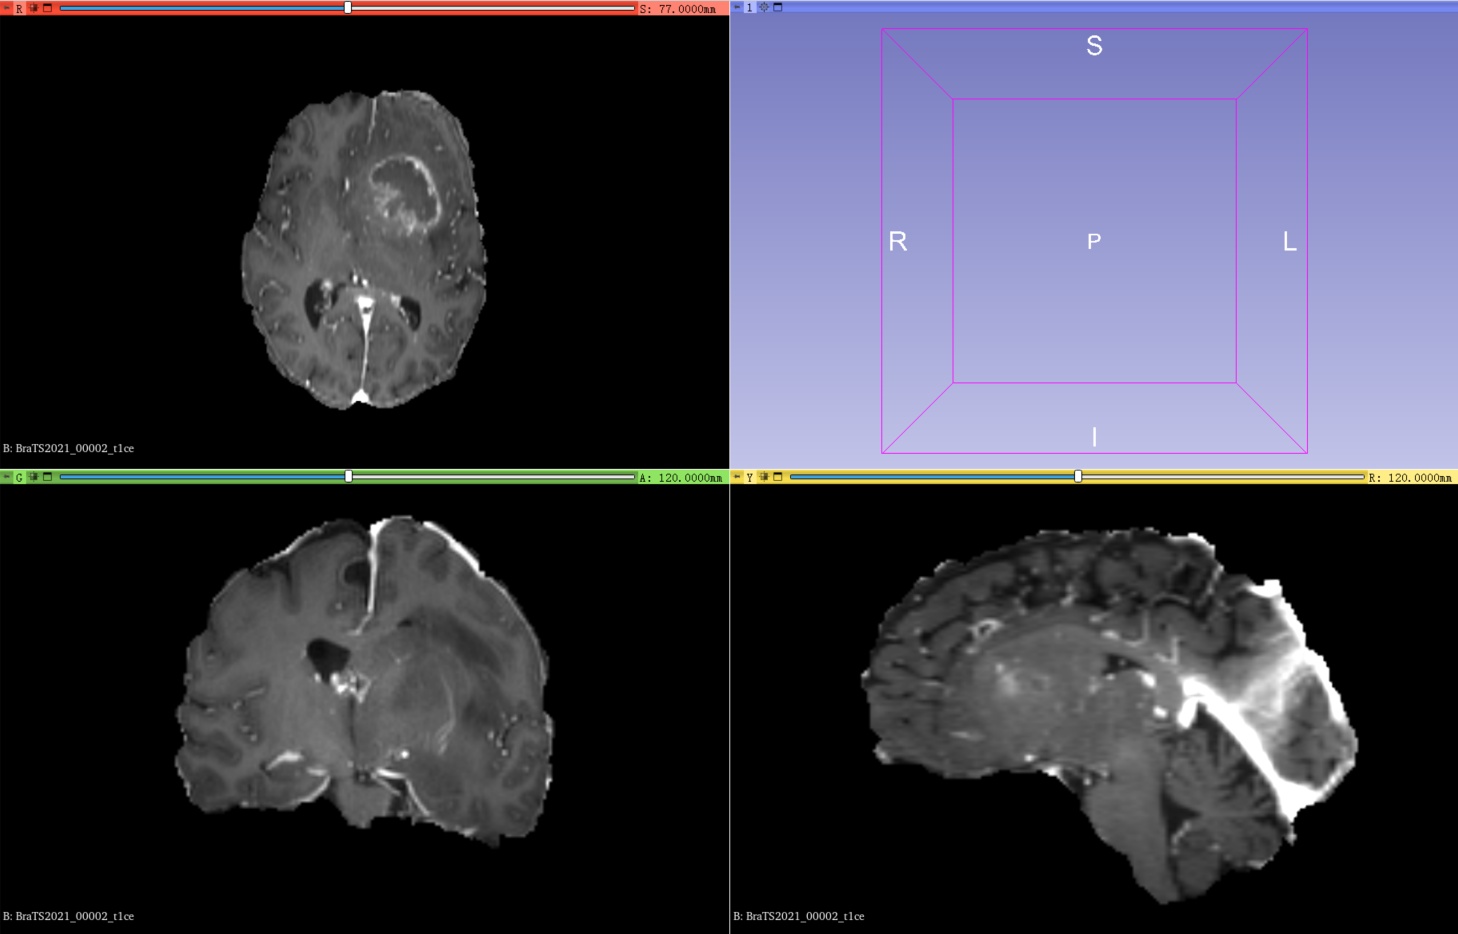

训练集其中一例MRI扫描(包含4个模态的3D图像以及1个共享标签)

1、在训练集中包含1251例核磁共振成像扫描,每例扫描包含4种模态的3D图像以及1个共享标签,其中4种模态分别是t1、t1ce、t2、flair:

T1对比增强成像(T1-weighted imaging with contrast enhancement, T1CE ):这种成像方式是在T1序列的基础上加入了造影剂,能够帮助检测到肿瘤和炎症等病变。T1CE序列主要用于显示肿瘤和炎症等异常组织。

BraTS2021_00002_t1ce.nii.gz |

4、可视化使用3D Slicer查看图像和标签,可以直观的了解自己要用的数据集。左上角代表在Axial(轴向)视角下,可以查看由上到下的脑部二维切片;左下角代表在Coronal(冠状)视角下,可以查看由前到后的脑部二维切片;右下角代表在Sagittal(矢状)视角下,可以查看由左到右的脑部二维切片。